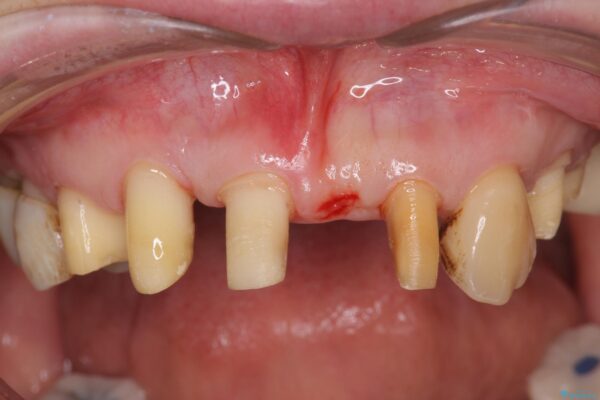

治療中

歯の総合的なマネージメントを行う包括的歯科治療の実践[ 歯周病・矯正・セラミック補綴 ] 治療中画像 歯の総合的なマネージメントを行う包括的歯科治療の実践[ 歯周病・矯正・セラミック補綴 ] 治療中画像 歯の総合的なマネージメントを行う包括的歯科治療の実践[ 歯周病・矯正・セラミック補綴 ] 治療中画像 歯の総合的なマネージメントを行う包括的歯科治療の実践[ 歯周病・矯正・セラミック補綴 ] 治療中画像 歯の総合的なマネージメントを行う包括的歯科治療の実践[ 歯周病・矯正・セラミック補綴 ] 治療中画像 歯の総合的なマネージメントを行う包括的歯科治療の実践[ 歯周病・矯正・セラミック補綴 ] 治療中画像 歯の総合的なマネージメントを行う包括的歯科治療の実践[ 歯周病・矯正・セラミック補綴 ] 治療中画像 歯の総合的なマネージメントを行う包括的歯科治療の実践[ 歯周病・矯正・セラミック補綴 ] 治療中画像 歯の総合的なマネージメントを行う包括的歯科治療の実践[ 歯周病・矯正・セラミック補綴 ] 治療中画像 歯の総合的なマネージメントを行う包括的歯科治療の実践[ 歯周病・矯正・セラミック補綴 ] 治療中画像 歯の総合的なマネージメントを行う包括的歯科治療の実践[ 歯周病・矯正・セラミック補綴 ] 治療中画像